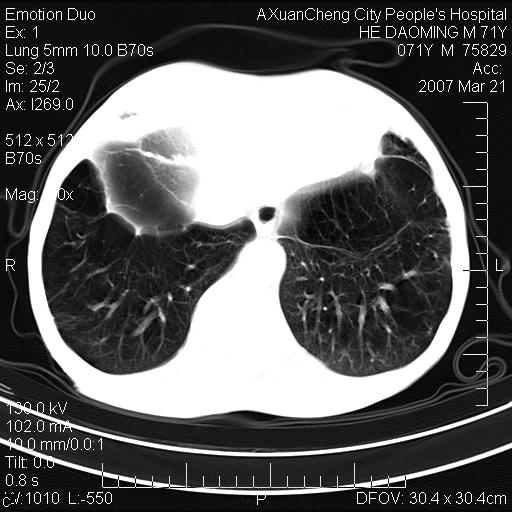

标题: CT7269:[原创] 咳嗽,咳痰,大家讨论右肺病变的部位

右侧相当于叶间软组织样密度ct值约50hu,请大家讨论是什么性者病变

考虑:慢性支气管炎合并全小型肺气肿、肺大泡、间质纤维化、感染,右斜裂积液。

慢性支气管炎,全小叶性肺气肿,右肺上.中叶肺大泡,伴有感染.支气管扩张.

考虑:慢性支气管炎合并右侧全小型肺气肿、肺大泡并感染、双肺间质纤维化,右斜裂积液。

如果患者变化一下体位扫描可分辨液平与斜裂的关系。